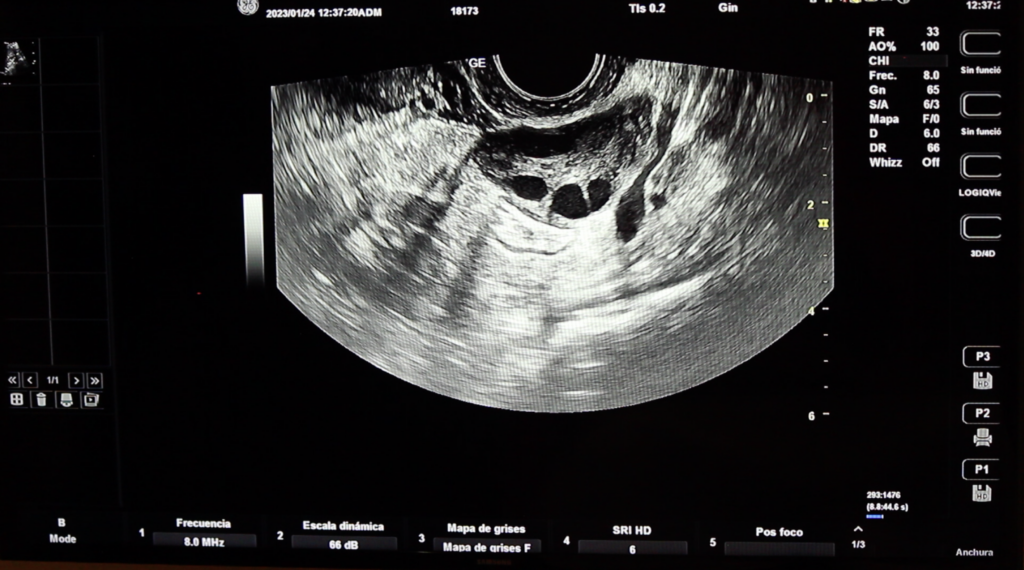

Mapeo de Endometriosis por Ultrasonido

It is a diagnostic study that evaluates areas where endometriosis is most frequent to appear. It is characterized by the use of transvaginal abdominal and pelvic ultrasound.

Esta técnica la realiza nuestro especialista en su consultorio. Dura aproximadamente entre 25 – 30 minutos y no tiene efectos adversos.